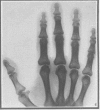

Congenital Familial Clubbing of the Fingers and Toes *